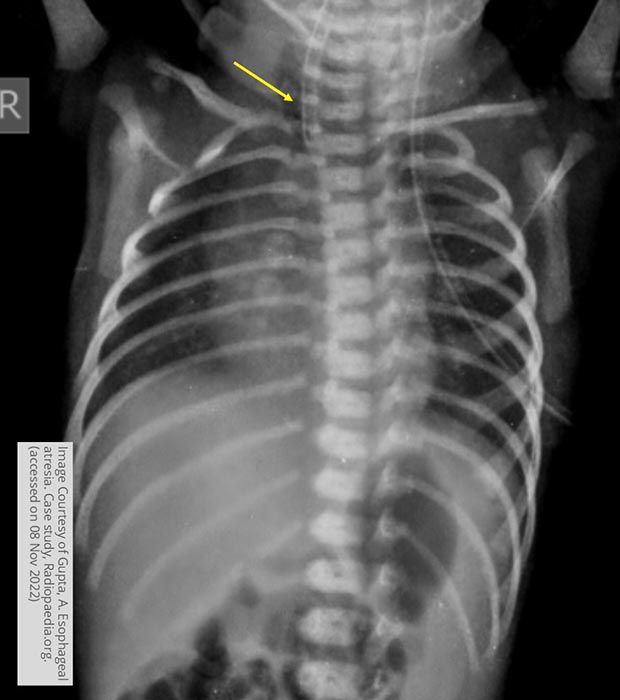

What is the key plain-film finding in esophageal atresia?

NG/OG tube coils in the proximal esophageal pouch and does not reach the stomach.

What does abdominal gas pattern indicate in TEF?

Presence or absence of bowel gas helps determine the type of TEF.